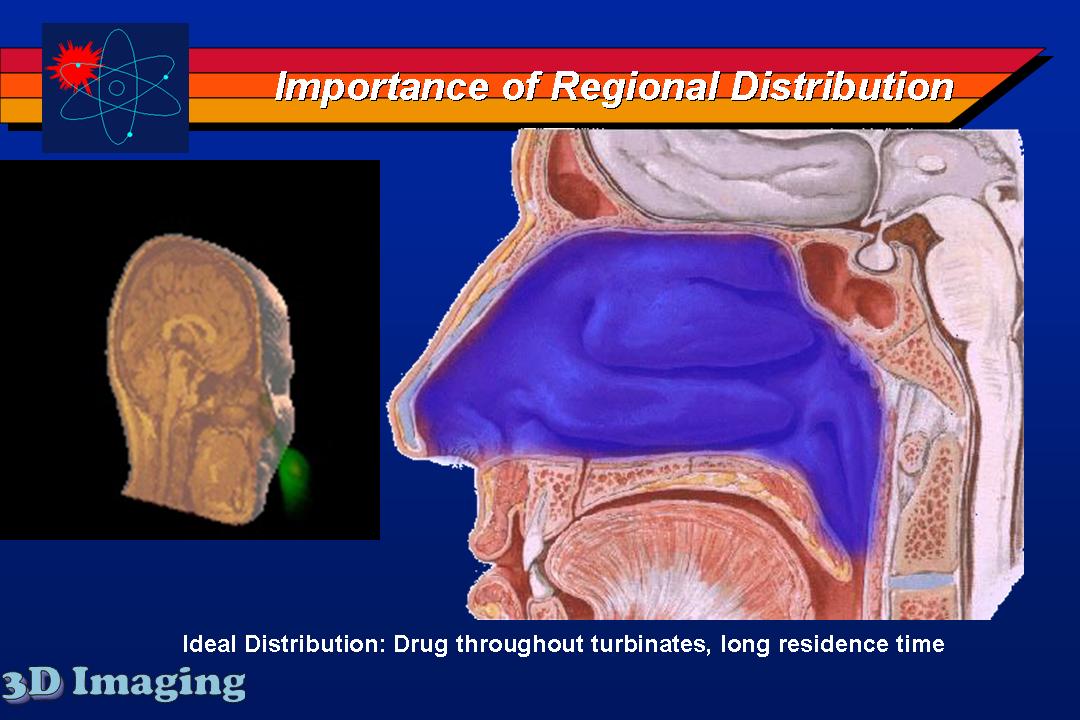

Several inhaled drug formulations were studied by radiolabeling the active ingredient (several different steriods) with C-11 or F-18, formulating that ingredient as the dosage form (different MDI, DPI, and nebulizer formulations), and performing quantitative PET studies of the regional biodistribution and kinetics.

Click on images to see additional examples, larger versions, and videos.